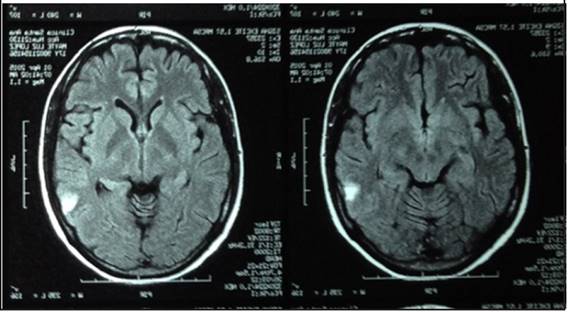

El día 13, hematología ordena inicio de Eculizumab por tratarse de SHUa. Al día siguiente de la aplicación, se observa franca respuesta hemodinámica, logrando disminuir la MAT y extubar a la paciente de manera programada. Se realiza RMN (figura 3) de control. Continúa infusión de Eculizumab según programación semanal. Posterior a tres semanas de manejo dirigido bloqueando el complemento, la paciente evolucionó de manera muy adecuada con mejoría de cifras tensionales, de disfunción hepática y con normalización de la función renal.